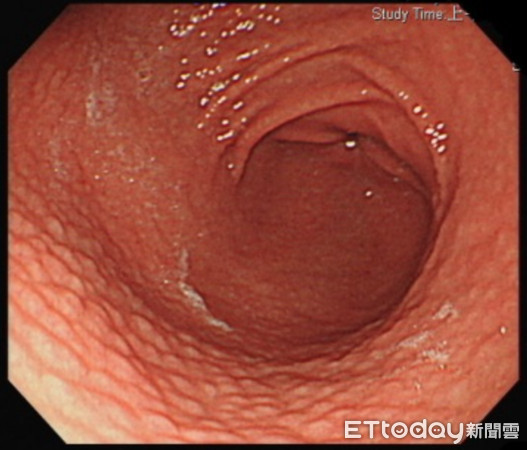

▲貧血又腹脹竟是「致癌菌」惹禍,他胃表皮長疙瘩如「炸雞皮」。(圖/記者嚴云岑翻攝)

28歲的張先生長年貧血,近一個月經常感到腹脹、難以消化至腸胃科就醫,經胃鏡檢查,發現胃靠近幽門的地方有廣泛性發炎,表面形成類似雞皮疙瘩般結節狀變化,看起來就像炸雞皮,十二指腸也有潰瘍過的疤痕。進一步檢查,才發現是幽門桿菌感染,雖經藥物治療後,以改善消化症狀,但長期貧血的問題仍有待持續追蹤。